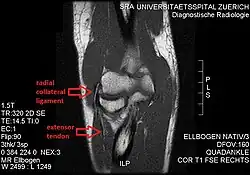

The radial collateral ligament (RCL), lateral collateral ligament (LCL), or external lateral ligament[Explain 1] is a ligament in the elbow on the side of the radius.

The composition of the triangular ligamentous structure on the lateral side of the elbow varies widely between individuals[1] and can be considered either a single ligament,[2] in which case multiple distal attachments are generally mentioned and the annular ligament is described separately, or as several separate ligaments,[1] in which case parts of those ligaments are often described as indistinguishable from each other.

In the latter case, the ligaments are collectively referred to as the lateral collateral ligament complex (LCLC), consisting of four ligaments:[1]

- the radial collateral ligament [proper] (RCL), from the lateral epicondyle to the annular ligament deep to the common extensor tendon[1]

- the lateral ulnar collateral ligament (LUCL), from the lateral epicondyle[3] to the supinator crest on the ulna. Near the attachment on the humerus this ligament is normally indistinguishable from the RCL and can be considered the posterior portion of it.[1] Martin 1958 described the distal part of the LUCL as "a definite bundle which normally crosses the annular band and gains attachment to the supinator crest, frequently to a special tubercle on that crest" but didn't name it.[4]

- the annular ligament (AL), from the posterior to the anterior margins of radial notch on the ulna, encircles the head of radius and holds it against the radial notch of ulna.[5]

- the accessory lateral collateral ligament (ALCL), from the inferior margin of the annular ligament to the supinator crest.